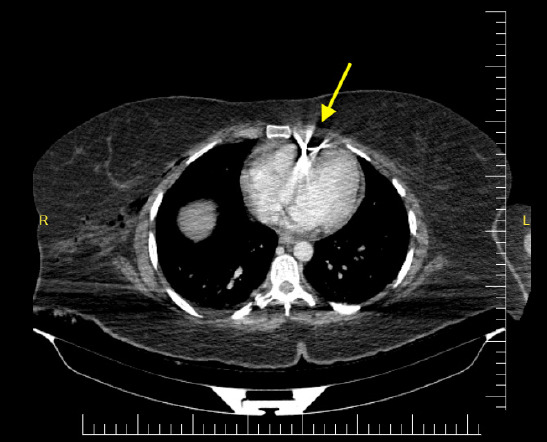

In conflict-affected regions such as Somalia, injuries resulting from terror-related explosions impose a substantial public health burden. Shrapnel injuries are frequently encountered and often lead to multiple trauma, with penetrating thoracic injuries among the most clinically significant. Although rare, cardiac trauma presents considerable diagnostic and therapeutic challenges for emergency physicians and trauma surgeons. While surgical intervention is typically indicated in hemodynamically unstable patients, the optimal management for retained intracardiac foreign bodies (FBs) in stable patients remains an area of clinical uncertainty. The decision between surgical removal and conservative observation is influenced by several factors, including hemodynamic stability, the presence of cardiac complications, and the characteristics of the retained object. We present a case of a hemodynamically stable patient in Somalia with a retained intracardiac shrapnel fragment following a terror-related explosion. Imaging studies, particularly transthoracic echocardiography, revealed a foreign body within the pericardial space, without evidence of tamponade or myocardial injury. Given the stable clinical course and absence of acute cardiac pathology, a non-operative strategy with close clinical and echocardiographic monitoring was adopted. The patient remained complication-free and was successfully managed. This case underscores the feasibility of conservative treatment in selected hemodynamically stable patients with intracardiac FBs and highlights the necessity of an individualized, multidisciplinary clinical approach in complex trauma scenarios.